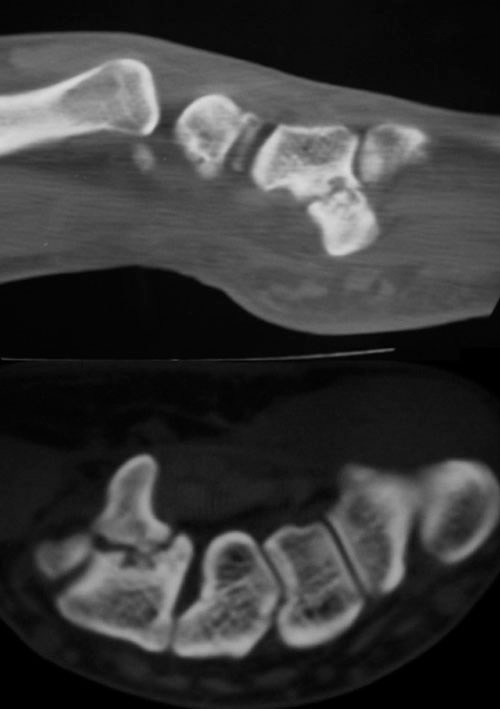

Figura 2: Radiografía de Fractura de la apófisis

uniforme del hueso ganchoso

- lesines óseas (hueso ganchoso),

- compresión en la arcada fibrosa del aductor del 5º dedo (figuras 2-4).

Lesiones traumáticas: Fracturas de los huesos del carpo (especialmente del ganchoso o pisiforme).